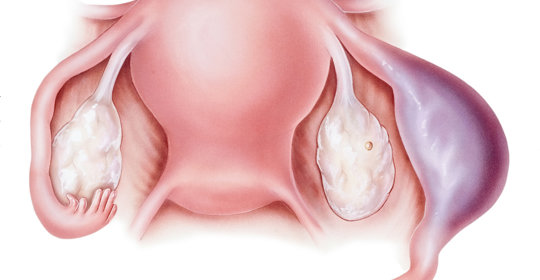

橫結腸息肉:便血腹痛與子宮息肉內分泌失調不同管理

子宮頸水腫:症狀、原因及預防

本文介紹了子宮頸糜爛與人類乳突病毒(HPV)(HPV)感染之間的關係以及子宮頸癌的一些常見症狀。子宮頸糜爛是子宮頸上皮細胞的一種病變,而HPV感染是導致子宮頸癌的主要原因之一。對於子宮頸糜爛患者來說,定期進行婦科檢查是非常重要的,可以早期發現並預防子宮頸癌的發生。同時,保持良好的個人衛生習慣也有助於減少HPV感染的風險。

子宮頸抹片檢查異常:處理流程與注意事項

懷孕初期腹痛:子宮外孕的臨床表現及處理措施

子宮頸舉痛:治療方法與護理注意事項

子宮頸囊腫:臨床表現與處理原則

子宮頸水腫:診斷與治療方法

子宮頸炎:診斷方法、原因及治療